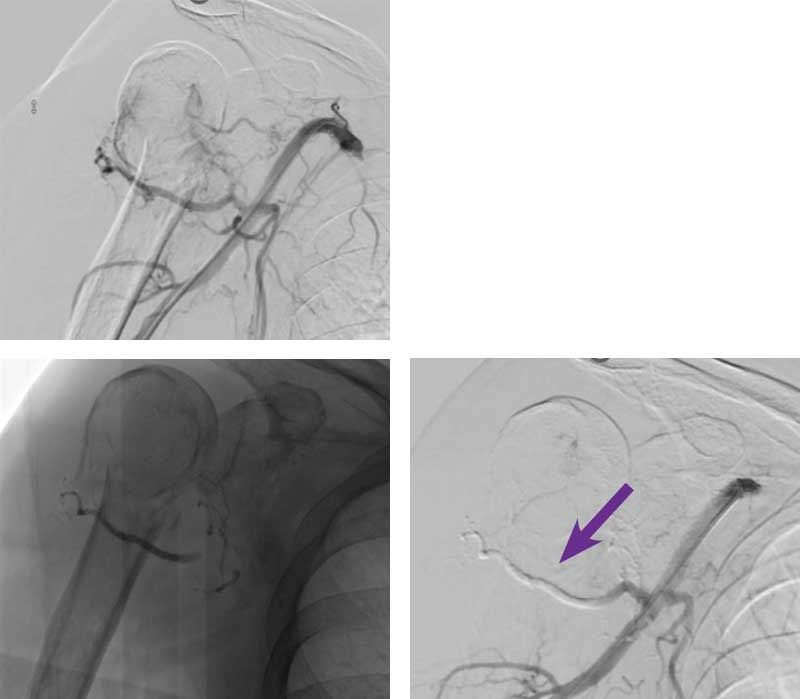

Pre-operative right humerus lesion embolization

Courtesy of Dr. Abhishek Kumar I Rutgers New Jersey Medical School

72-year-old man with history of multiple myeloma presented with a right humerus lytic lesion and limited range of motion. Interventional Radiology was consulted for pre-operative embolization prior to surgical fixation.

Intervention used

Right radial access was gained and a 5 F sheath was placed. A 5 F angled catheter was placed in the right subclavian artery and an angiogram was performed. Angiography revealed a hypervascular lesion in the right humerus supplied by multiple vessels. A 2.8 F microcatheter and 0.014” wire were used to select the first vessel supplying the lesion and embolization performed with a 0.3 cc aliquot of Obsidio Embolic. The microcatheter was removed, flushed and used again to select two additional branches where 0.2 cc of Obsidio Embolic was deployed into each vessel. A total of 3 vessels were embolized with a total of approximately 0.7 cc of Obsidio Embolic. Obsidio Embolic casts in the vessels is highlighted in post-imaging. Completion angiography via the base catheter showed complete embolization of the left internal mammary artery. A still image shows Obsidio Embolic cast occluding the vessel.

Outcome

The patient underwent successful surgical fixation with minimal blood loss.

Scan images from Obsidio pre-operative right humerus lesion embolization case.